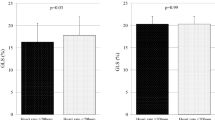

Univariate analysis using the logistic regression model showed that type 2 DM and presence of overweight/obesity, hypertriglyceridemia, nephropathy, neuropathy, and retinopathy were associated with GLS < 18%. The odds ratio (OR) and 95% confidence interval (CI) for each of these variables are given in Table 2. An important finding of the multivariate logistic regression analysis was that type 2 DM, overweight/obesity, hypertriglyceridemia, nephropathy and neuropathy were independently associated with GLS < 18%, and nephropathy was found to be the highest risk factor of GLS < 18% (OR: 5.26; 95% CI 2.111-13.12; p < 0.001). The incremental advantage of using sequential logistic regression models for the prediction of GLS < 18% is shown in Figure 2. A model based on clinical variables including, gender, type 2 DM and DM duration (χ 2 = 24.1) was improved by addition of overweight/obesity and hypertriglyceridemia (χ 2 = 45.6, p < 0.001) and further improved by addition of nephropathy and neuropathy (χ 2 = 70.2, p < 0.001).

The incremental advantage of using sequential logistic models for the prediction of GLS < 18%. A model based on clinical variables including gender, type 2 diabetes mellitus (DM) and DM duration (χ 2 = 24.1) was improved by the addition of hypertriglyceridemia and overweight /obesity (χ 2 = 45.6; p < 0.001), and further improved by the addition of nephropathy and neuropathy (χ 2 = 70.2; p < 0.001).